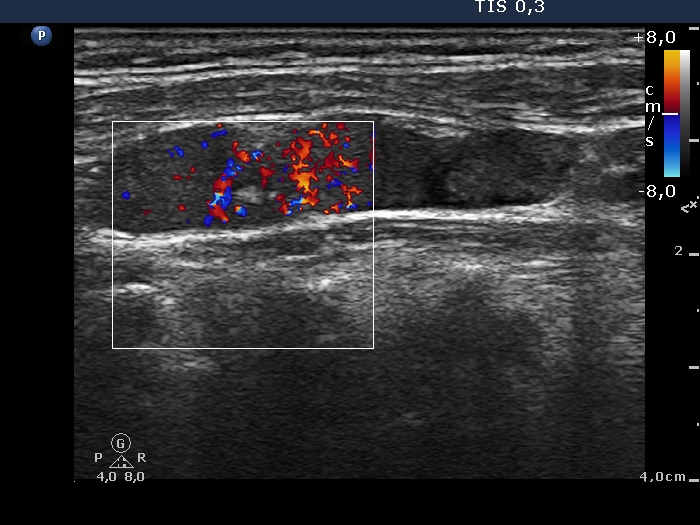

Follow-up examination 17 months after first visit (second and third rows):

Functional state: subclinical hyperthyroidism (TSH undetectable, FT4 21.1 pM/L, FT3 6.68 pM/L).

Ultrasonography: The echogenicity index of the thyroid was 50%. The vascularization was not significantly increased. There was a large hypoechogenic, inhomogeneous nodule in the upper part of the left lobe. Both the intranodular and the perinodular blood flows were increased.

2. It is worth analyzing the video recorded at the second examination. Both the nodule and the extranodular part present fibrotic changes, moreover the inhomogeneity of the extranodular part is more pronounced than that of the nodule.